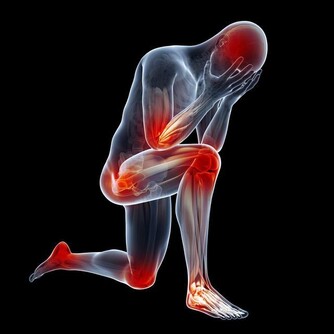

一說起尿毒症可能大家現在都不太陌生,尿毒症是指身體不能通過腎臟產生尿液,把身體代謝所產生的廢物,還有多餘的水分排出體外而引起的毒害,尿毒症是腎功能下降

腎臟是 所以在我們的日常生活當中,需要通過合理的方式來保護腎臟的健康,以免腎臟功能受到損傷,影響身體健康。

結語:尿毒症對身體的傷害是毀滅性的,目前的醫療水平無法徹底根治尿毒症。那麼我們就應該防患於未然,改變不良的生活習慣,這樣才能更好的保護自己的腎臟。